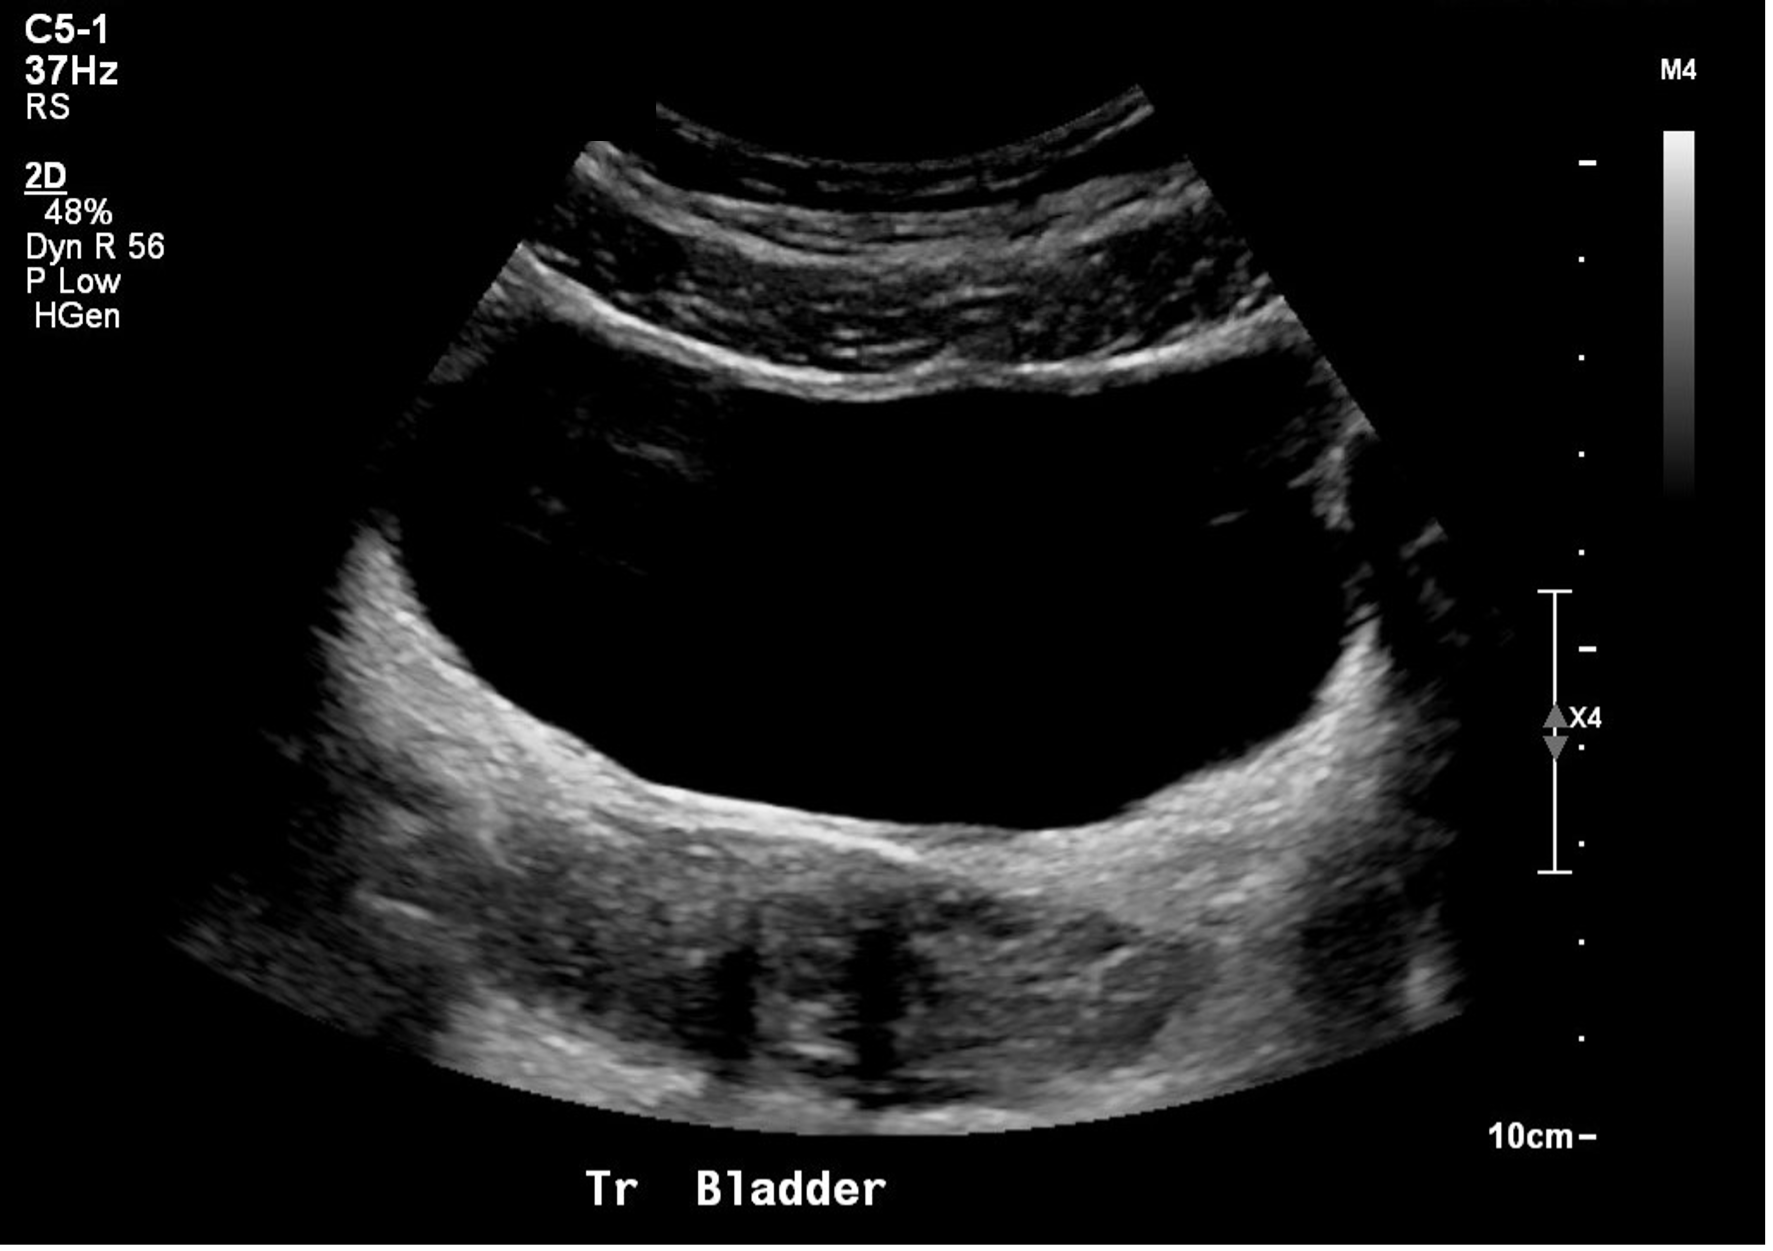

The shape and relationships of the bladder on ultrasound examination will depend on its degree of filling. The sagittal view is triangular (figure 10), and the transverse view is rectangular (figure 11). That said, the shape varies depending on bladder fullness. When distended, the bladder walls appear thinner compared to a thicker appearance when less distended (figure 12).

Figure 11: Normal bladder in the transverse plane

Figure 12: Transverse view of a near empty bladder with thicker walls

The bladder will appear as an anechoic cavity surrounded by echogenic walls.